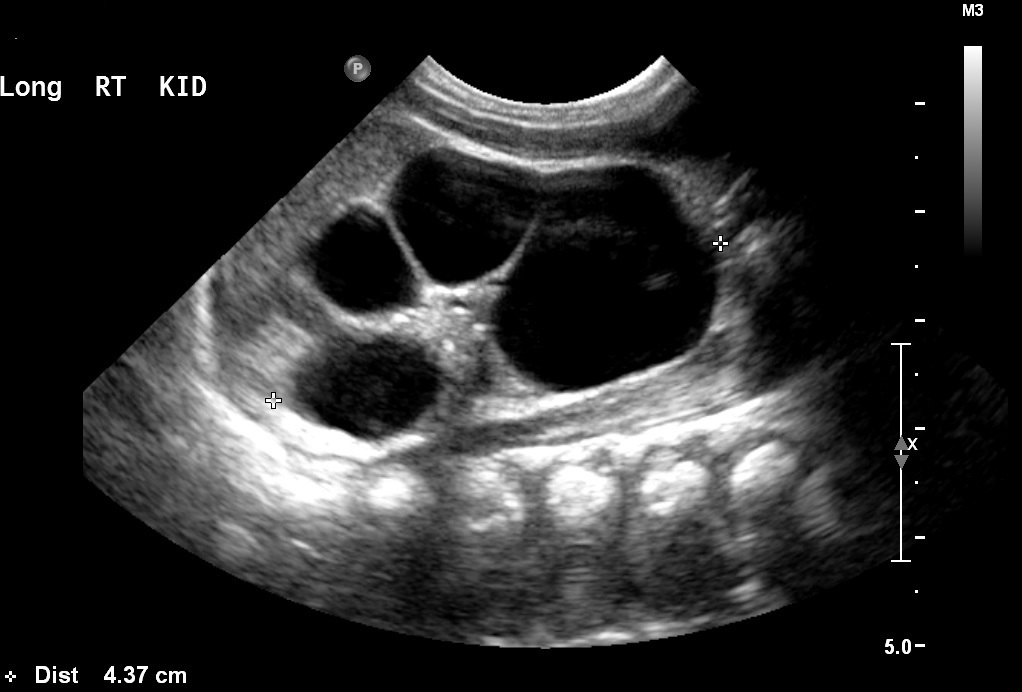

Multicystic dysplastic syndrome

Wolffian Duct

What pulmonary disease is this patient likely to develop?